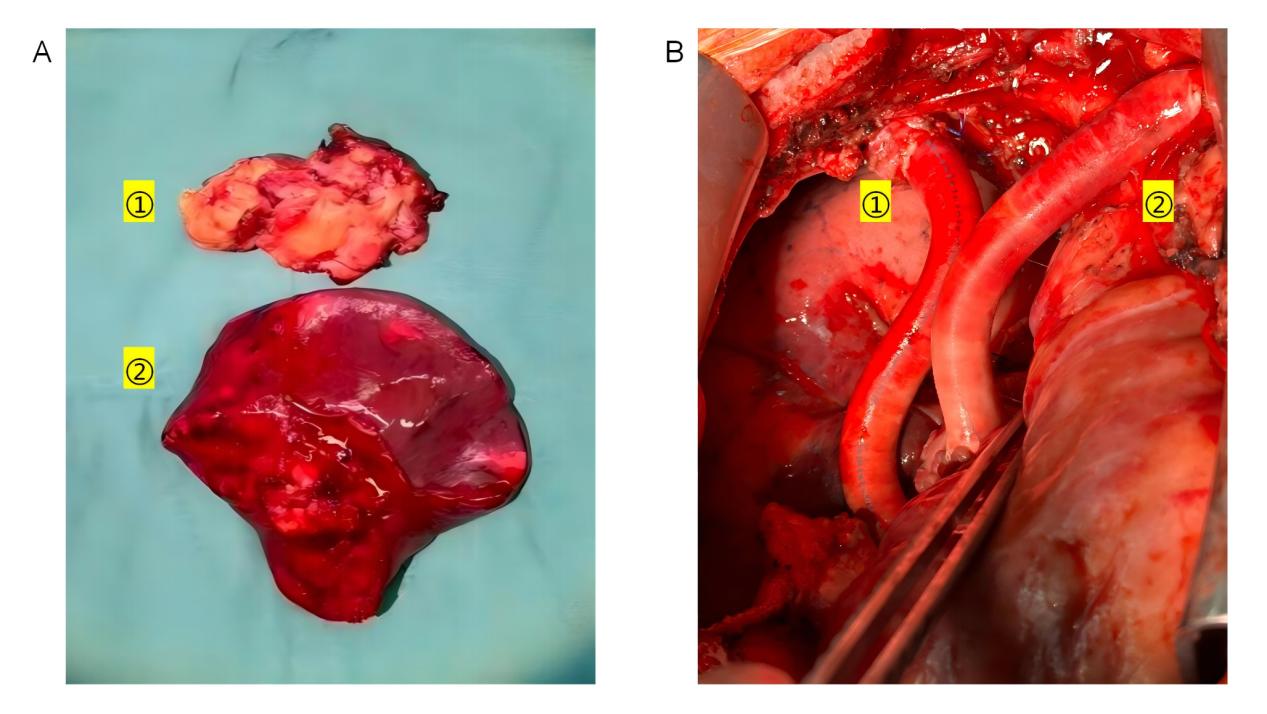

A:切除的肿瘤组织:①右心房及上腔静脉肿瘤,②右肺上叶;

B:重建的血管通路:①:自右侧无名静脉至重建的右心房,②自左侧无名静脉至右心耳。